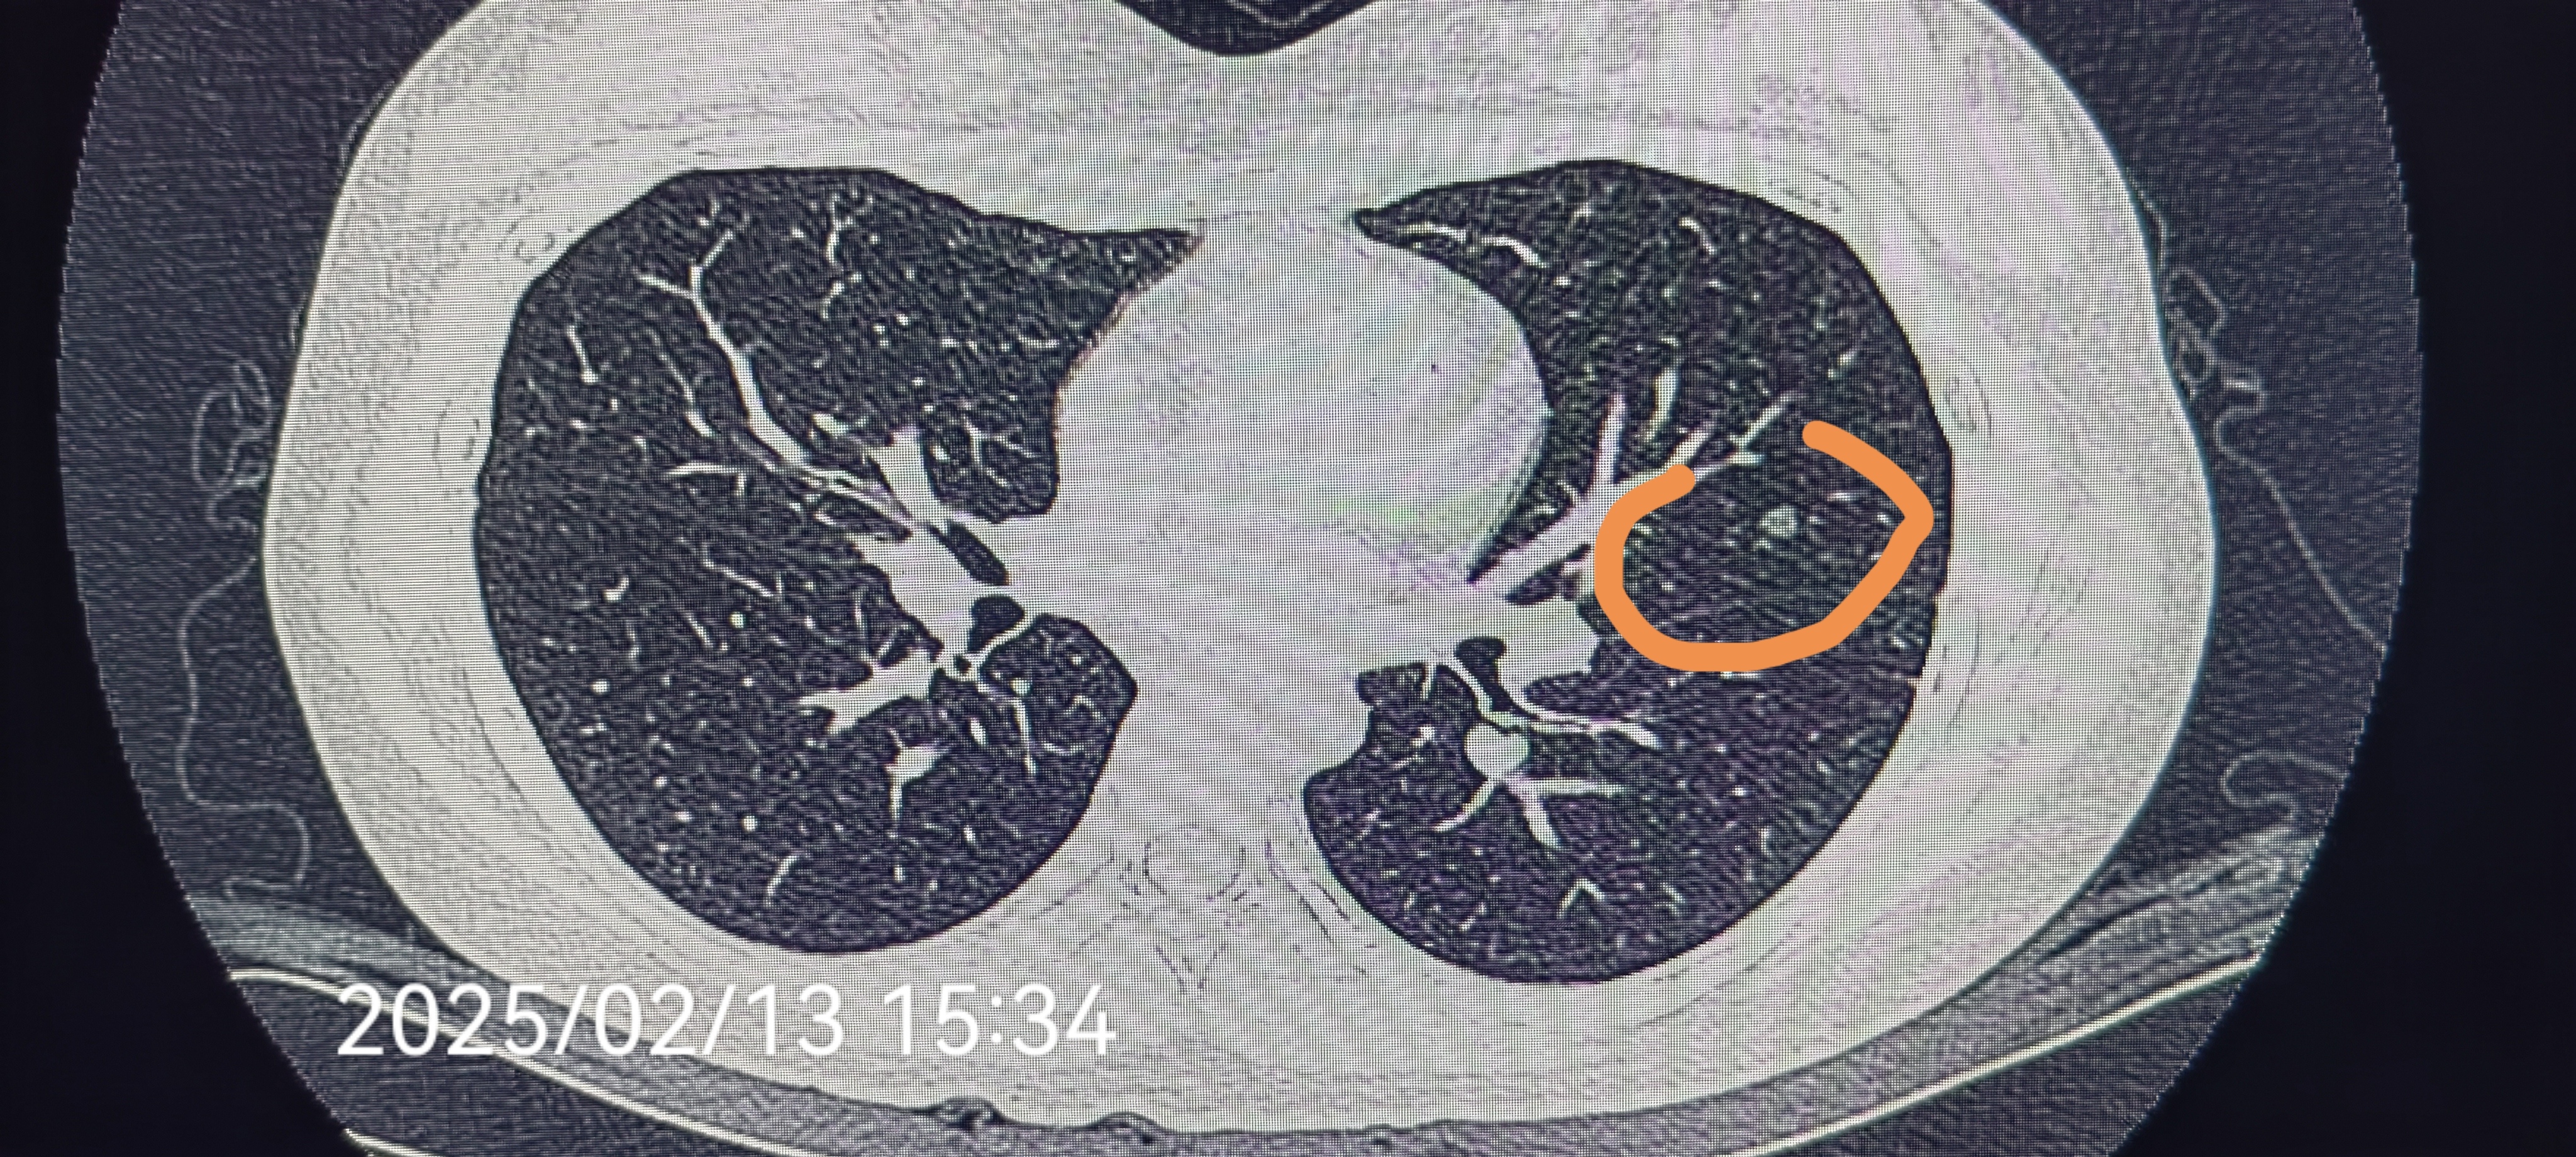

肺结节穿刺活检病理良性,抗炎治疗缩小.老年女性,因咳嗽咳痰